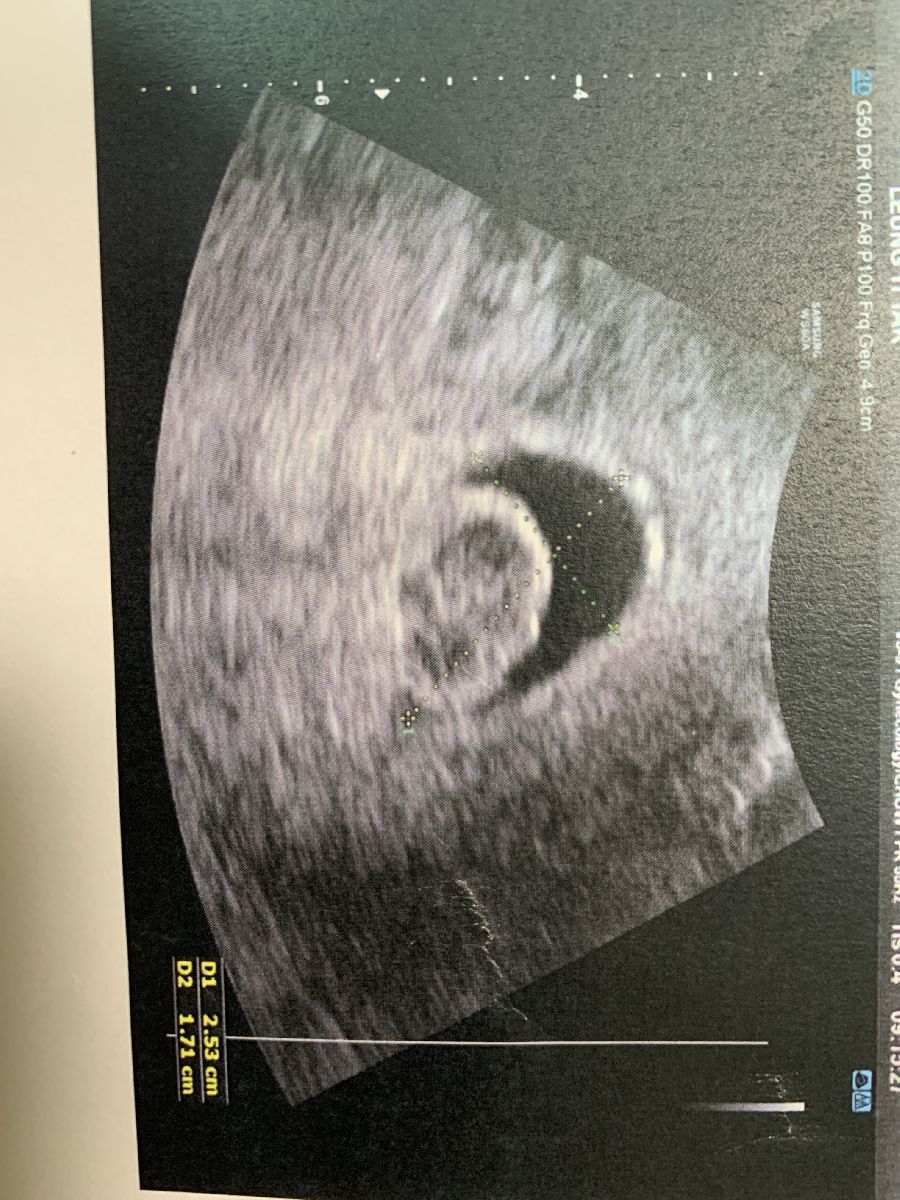

五週半胎囊

照了陰超

胎囊的大小跟周數附合

未有營養囊或胚胎,但見到一塊白色的

醫生也說無法確定是甚麼

有可能是不正常的胎,也可能隨著胎囊生長而相對不影響

我在網上找許久也沒有類似的情況

好怕怕 會是不正常嗎